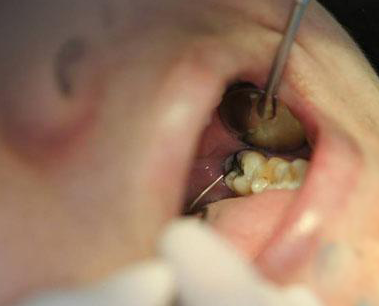

蛀牙。由于智齿的位置很里面,平时刷牙不容易刷干净,更容易有残留的食物,加快细菌感染蛀的更深,这种情况建议拔除。